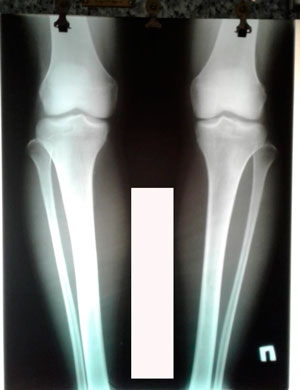

Исходник - 21 год.

Дата операции - 21.08.2020

дата снятия аппаратов - 04.11.2020